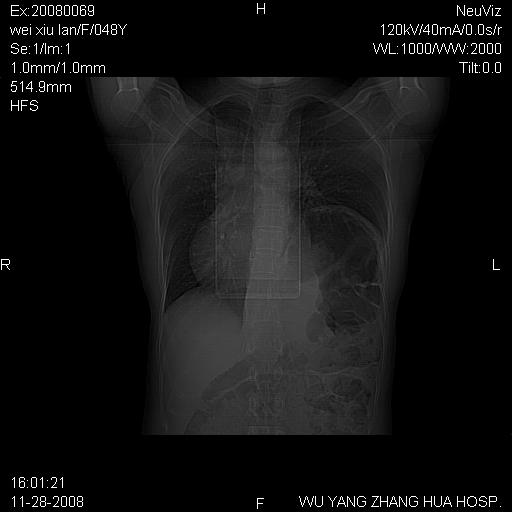

标题: CT16847:女,48岁,咳嗽,发热两日,平常偶有上腹部不适。 [打印本页]

标题: CT16847:女,48岁,咳嗽,发热两日,平常偶有上腹部不适。

能否考虑食管裂孔疝?请老师们多多指教。

支持左侧膈疝,心脏受压右移.

胃、脾脏及部分肠管明显升高,并压迫心脏移位,

首先考虑:左侧膈疝。

左侧胸腔内见胃肠及脾脏影

支持膈疝

左膈顶及肋膈角均上移,膈面光滑,考虑左膈肌麻痹